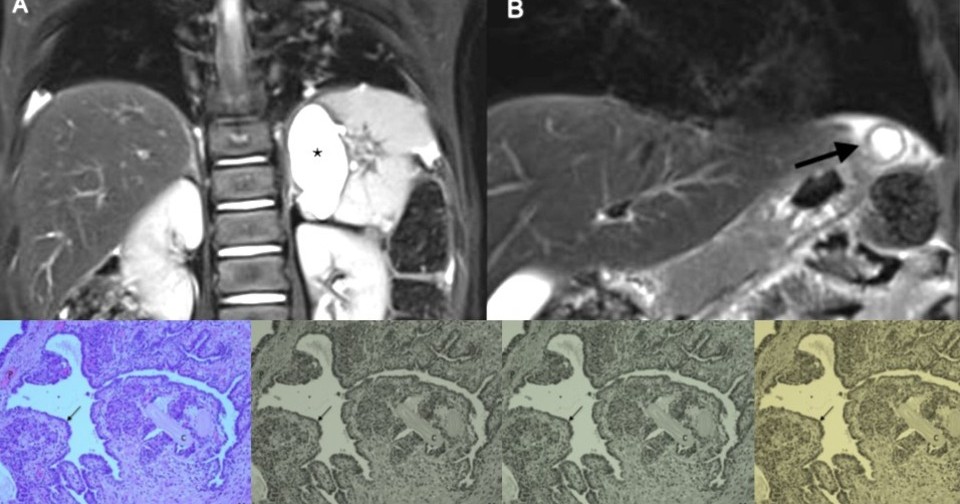

Ультразвуковое исследование в возрасте четырех месяцев вновь выявило кистозную структуру сзади от желудка, тесно связанную с селезенкой, левым надпочечником и левой почкой, ее размер несколько увеличился. В 2,5 года киста выросла до 3,3 × 2,7 × 2,0 кубических сантиметров, а рядом появилась еще одна кистозная структура, тесно связанная с желудком и поперечной ободочной кишкой. Магнитно-резонансная томография подтвердила, что большее образование — это дупликационная киста желудка, а меньшее — дупликационная киста кишки. При этом у девочки не было никаких симптомов или жалоб.

В четыре года ребенку провели резекцию обеих кистозных образований. Малая структура оказалась сальниковой кистой, а большая — дупликационной кистой, которая имела общую стенку с большой кривизной желудка и не сообщалась с его просветом. Полость кисты содержала серозно-слизистую жидкость.

Через три дня после операции ребенка выписали из больницы без осложнений. Гистологическое исследование показало, что небольшое поверхностное образование оказалось псевдокистой. А более крупная структура все же была дупликационной кистой желудка с эпителием, похожим на дыхательный, с элементами ткани поджелудочной железы. В обеих кистах не обнаружилось признаков озлокачествления.